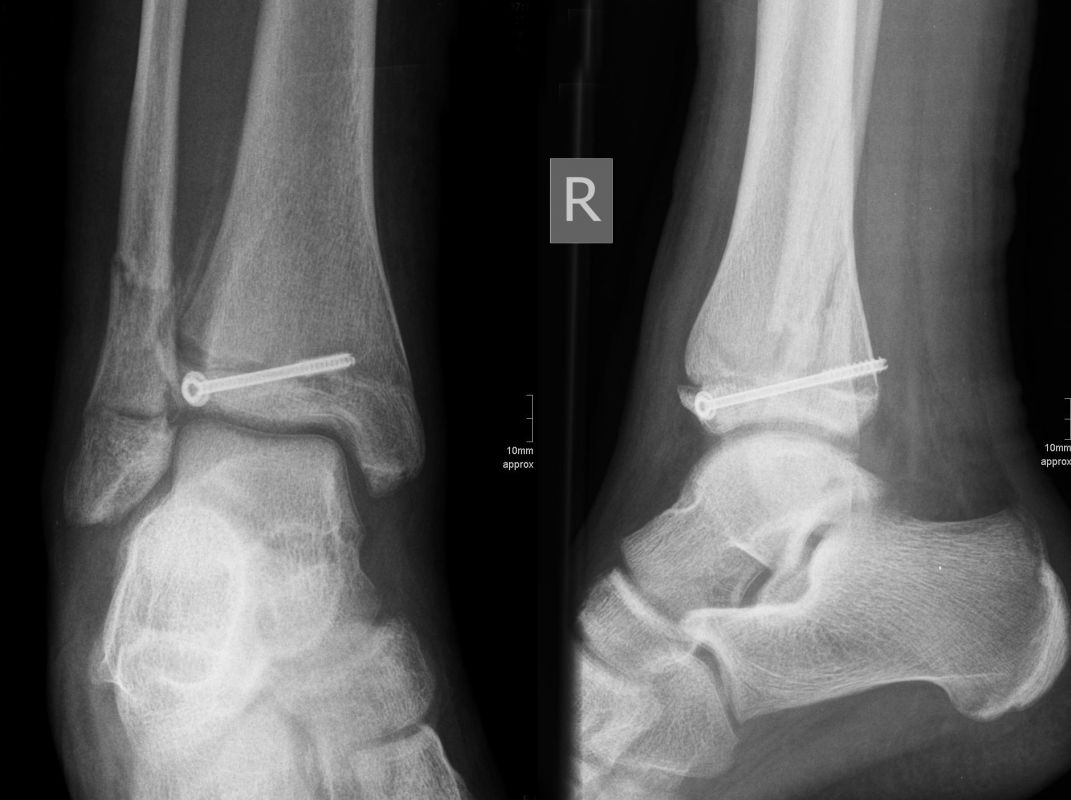

Behandlungsziel ist die exakte Rekonstruktion der Gelenkfläche sowie die Minimierung des Risikos einer späteren Wachstumsstörung. Dislozierte Frakturen werden offen reponiert, die Osteosynthese erfolgt mit einer Kleinfragmentschraube. Finden sich viele kleine Fragmente kann eine K-Draht Osteosynthese durchgeführt werden. Wird der Innenknöchel operiert, kann bei gleichzeitiger hochgradiger lateraler Instabilität eine Rekonstruktion des lateralen Bandapparats durchgeführt werden. Fibula Frakturen stellen sich meist spontan ein, sodass hier keine zusätzliche Osteosynthese notwendig ist.

Nach der Osteosynthese wird die Fraktur für ca. vier Wochen in einem Unterschenkelgips ruhiggestellt. Bei Schmerzfreiheit der Frakturzone erfolgt anschließend eine schmerzadaptierte Belastungssteigerung über weitere zwei Wochen. Sobald unter Alltagsbedingungen Beschwerdefreiheit besteht kann die sportliche Belastung langsam gesteigert werden. Kirschnerdrähte werden 6-8 Wochen postoperativ, Schrauben nach zwölf Wochen entfernt. Es empfiehlt sich klinische und radiologische Kontrollen im Abstand von 6 Monaten bis zum Wachstumsabschluss durchzuführen, um ein mögliches Fehlwachstum frühzeitig zu erkennen.